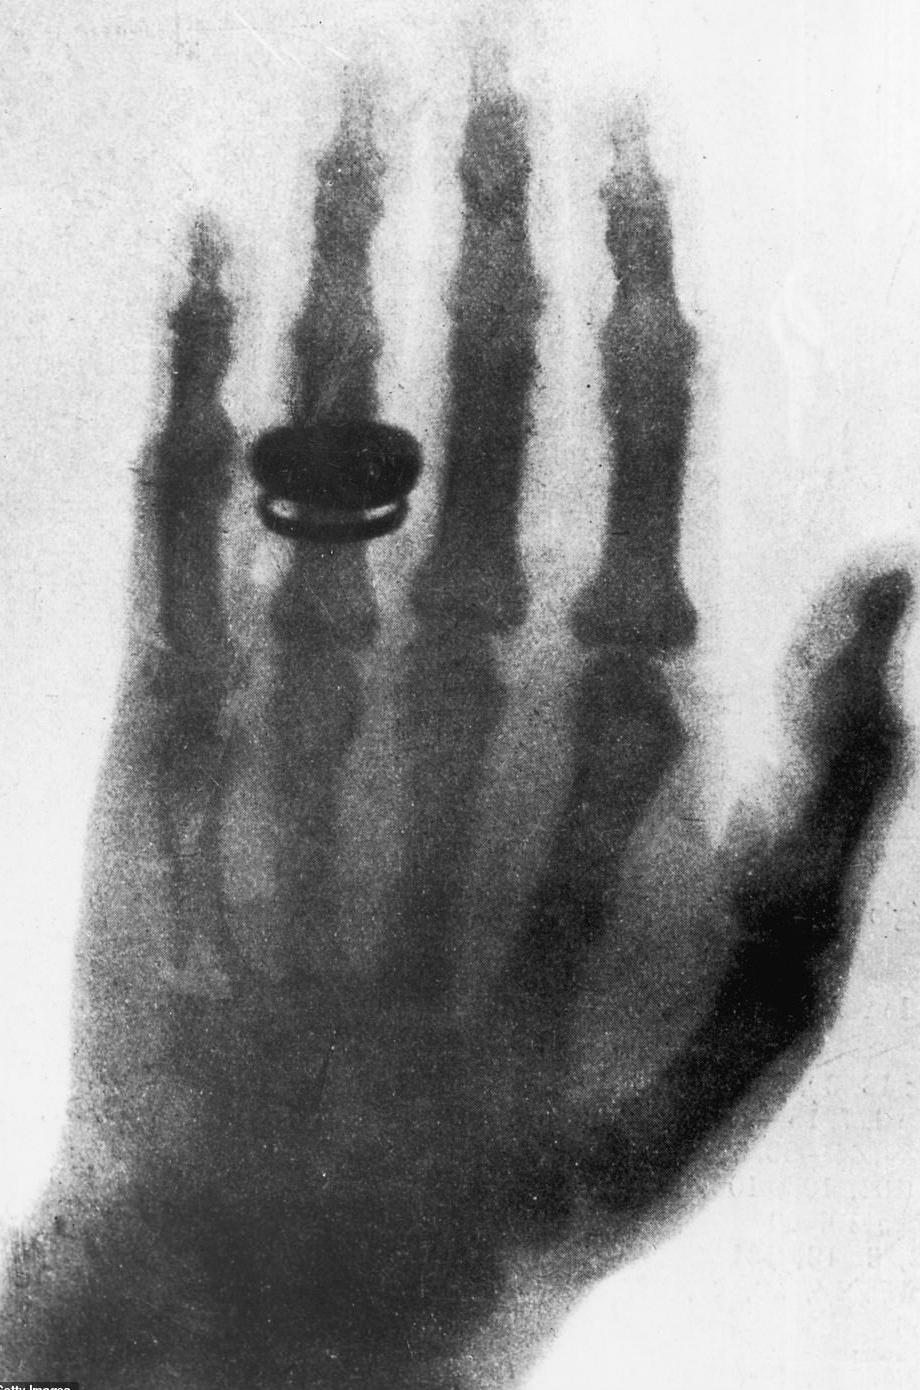

Även professor Franz Exner i Wien hade nämligen fått en nyårshälsning. Han brukade hålla ett öppet hus för sina bekanta på lördagkvällarna. Denna kväll visade han upp Röntgens manuskript med tillhörande bilder. Inte minst bilden på Röntgens hustru Berthas hand, tagen den 22 december 1895, väckte stor uppmärksamhet. Bild 2. En av gästerna, Ernst Lecher, nybliven professor i fysik i Prag efter Ernst Mach, bad att få låna bilderna och manuskriptet. Han ville visa nyheten för sin far Zacharias som var redaktör för dagstidningen Die Presse i Wien. Som gammal journalist kände Zacharias Lecher igen en stor nyhet och skrev om den i tidningen redan nästa dag, söndagen den 5 januari.2 Två dagar senare efter Trettondagen kom en kompletterande artikel med djupare vetenskapliga förklaringar till de nya strålarna där säkert sonen fysikprofessorn hade hjälpt till.

Bild 3. Rapport om Röntgens upptäckt i Svenska Dagbladet 10 januari 1896. Bild 1. Röntgens försöksuppställning med från vänster vakuumpump, Hittorff-rör och Ruhmkorff induktionsspole. Bild 2. Den första röntgenbilden av Bertha Röntgens hand. Bild 4. Annons i Svenska Dagbladet november 1902. Ortopeden Patrik Haglund har även ett röntgenlaboratorium. Mats Geijer